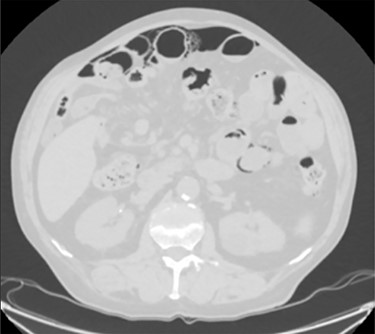

PCI first documented by Du Vernoy in 1783 [4] refers to the intraoperative or radiological findings of intramural gas-filled cysts in the bowel wall (Fig. 4). PCI can easily mimic pneumoperitoneum on radiological imaging as CT, being a very sensitive examination, may show even minimal circumferential gas collections outside the bowel lumen or misrepresent some findings [5]. Liu et al. [6] found that PCI was misdiagnosed as a surgical abdomen in up to 27% of cases resulting in unnecessary operation. It is important to differentiate idiopathic PCI with a secondary form of this condition known as pneumatosis intestinalis which is not in fact a disease but a rare finding characterized by the presence of gas in the submucosal and/or subserosal of the bowel wall that may result from an underlying pathological process (Table 2). PCI has a reported incidence in general population of 0.03% on autopsy series and up to 0.37% in CT series. Its prevalence is still unknown [7]. However, Adachi et al. [8] in a retrospective, single-center study found 24.7% of PCI cases in the selected group affected by pneumoperitoneum. PCI involves most commonly the small and large bowel (respectively 42% and 36% of cases; in 22% is concomitantly present), but could also involve the mesentery and omentum [7]. Physiopathology remains still unclear although some hypotheses have been proposed such as: the ‘mechanical theory’ where an increased pressure of intraluminal gas secondary to mechanical problems breach the mucosal or serosal layers (i.e. blunt trauma, persistent vomiting, ileus or endoscopy); the ‘bacterial theory’ where an excess of intraluminal bacterial production of nitrogen gas diffuse through the bowel wall; the ‘chemical theory’ where malnutrition can prevent the digestion of carbohydrates and increased bacterial fermentation in the intestine; the ‘pulmonary theory’ that refers to increased intraluminal bowel pressure due to the respiratory system [9].